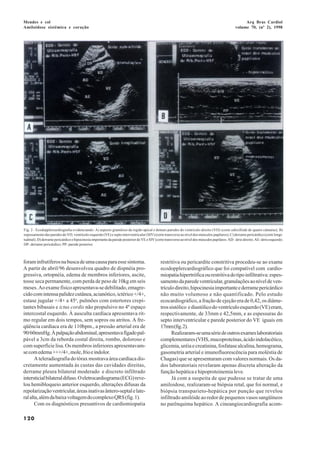

Correspondência: Rosana G. G. Mendes - Rua Tibiriça, 1094/802 - 14015- 120 -   Fig. 1 - A) Radiografia do tórax evidenciando cardiomegalia à custa das cavidades

Ribeirão Preto, SP                                                             direitas; B) eletrocardiograma mostrando, hemibloqueio anterior esquerdo, altera-

Recebido para publicação em 1/9/97                                             ções difusas da repolarização ventricular e áreas inativas ântero-septal e lateral alta,

Aceito em 3/12/97                                                              além de baixa voltagem do complexo QRS.

A teleradiografia do tórax mostrava área cardíaca dis-                                 Chagas) que se apresentaram com valores normais. Os da-

cretamente aumentada às custas das cavidades direitas,                                        dos laboratoriais revelaram apenas discreta alteração da

derrame pleura bilateral moderado e discreto infiltrado                                       função hepática e hipoproteinemia leve.

intersticial bilateral difuso. O eletrocardiograma (ECG) reve-                                      Já com a suspeita de que pudesse se tratar de uma

lou hemibloqueio anterior esquerdo, alterações difusas da                                     amiloidose, realizaram-se biópsia retal, que foi normal, e

repolarização ventricular, áreas inativas ântero-septal e late-                               biópsia transparieto-hepática por punção que revelou

ral alta, além da baixa voltagem do complexo QRS (fig. 1).                                    infiltrado amilóide ao redor de pequenos vasos sangüíneos